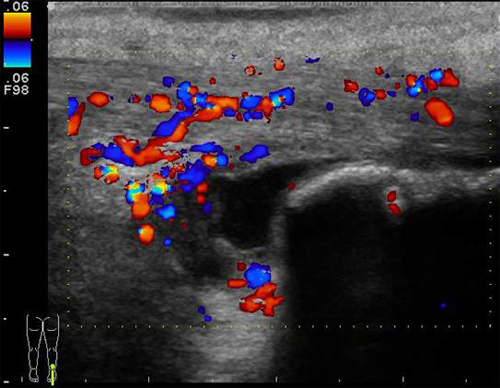

Exempel hälsena

Exempel hälsena  Fråga oss